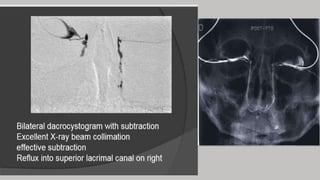

FILMS

Occipito mental –immediately following the injection to show filling and

emptying of the nasolacrimal duct

Lateral

When catheter is used

1st film-as plain film for subtraction

2nd film-when 1 ml of CM has been injected

3rd film-injection completed

The radiographs are then processed and subtracted

DCG

Technique Note

• It is normal practice to image both sides (comparison)

• It is preferable to inject both sides at the same time

• Collimate the X-ray beam to include the orbits superiorly and laterally

and the maxillary PNS inferiorly